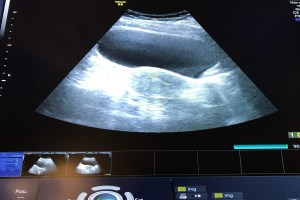

The embryo transfer is done on a full bladder. That’s really the most difficult part of the procedure. The catheter makes it’s way through my cervix easily and we watch the ultrasound screen without blinking to see the release of the embryo into my uterus. I beg that little embryo to attach and become our baby. Today is a good day. Today gives me the chance to become a mother. I’m full of hope.